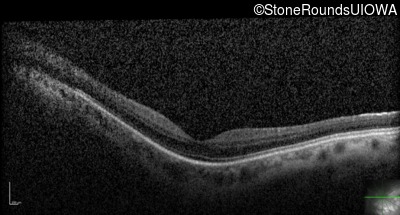

Optical Coherence Tomography - Right - 20/40 +2

Exemplar / OCT Stack

OCT Stack